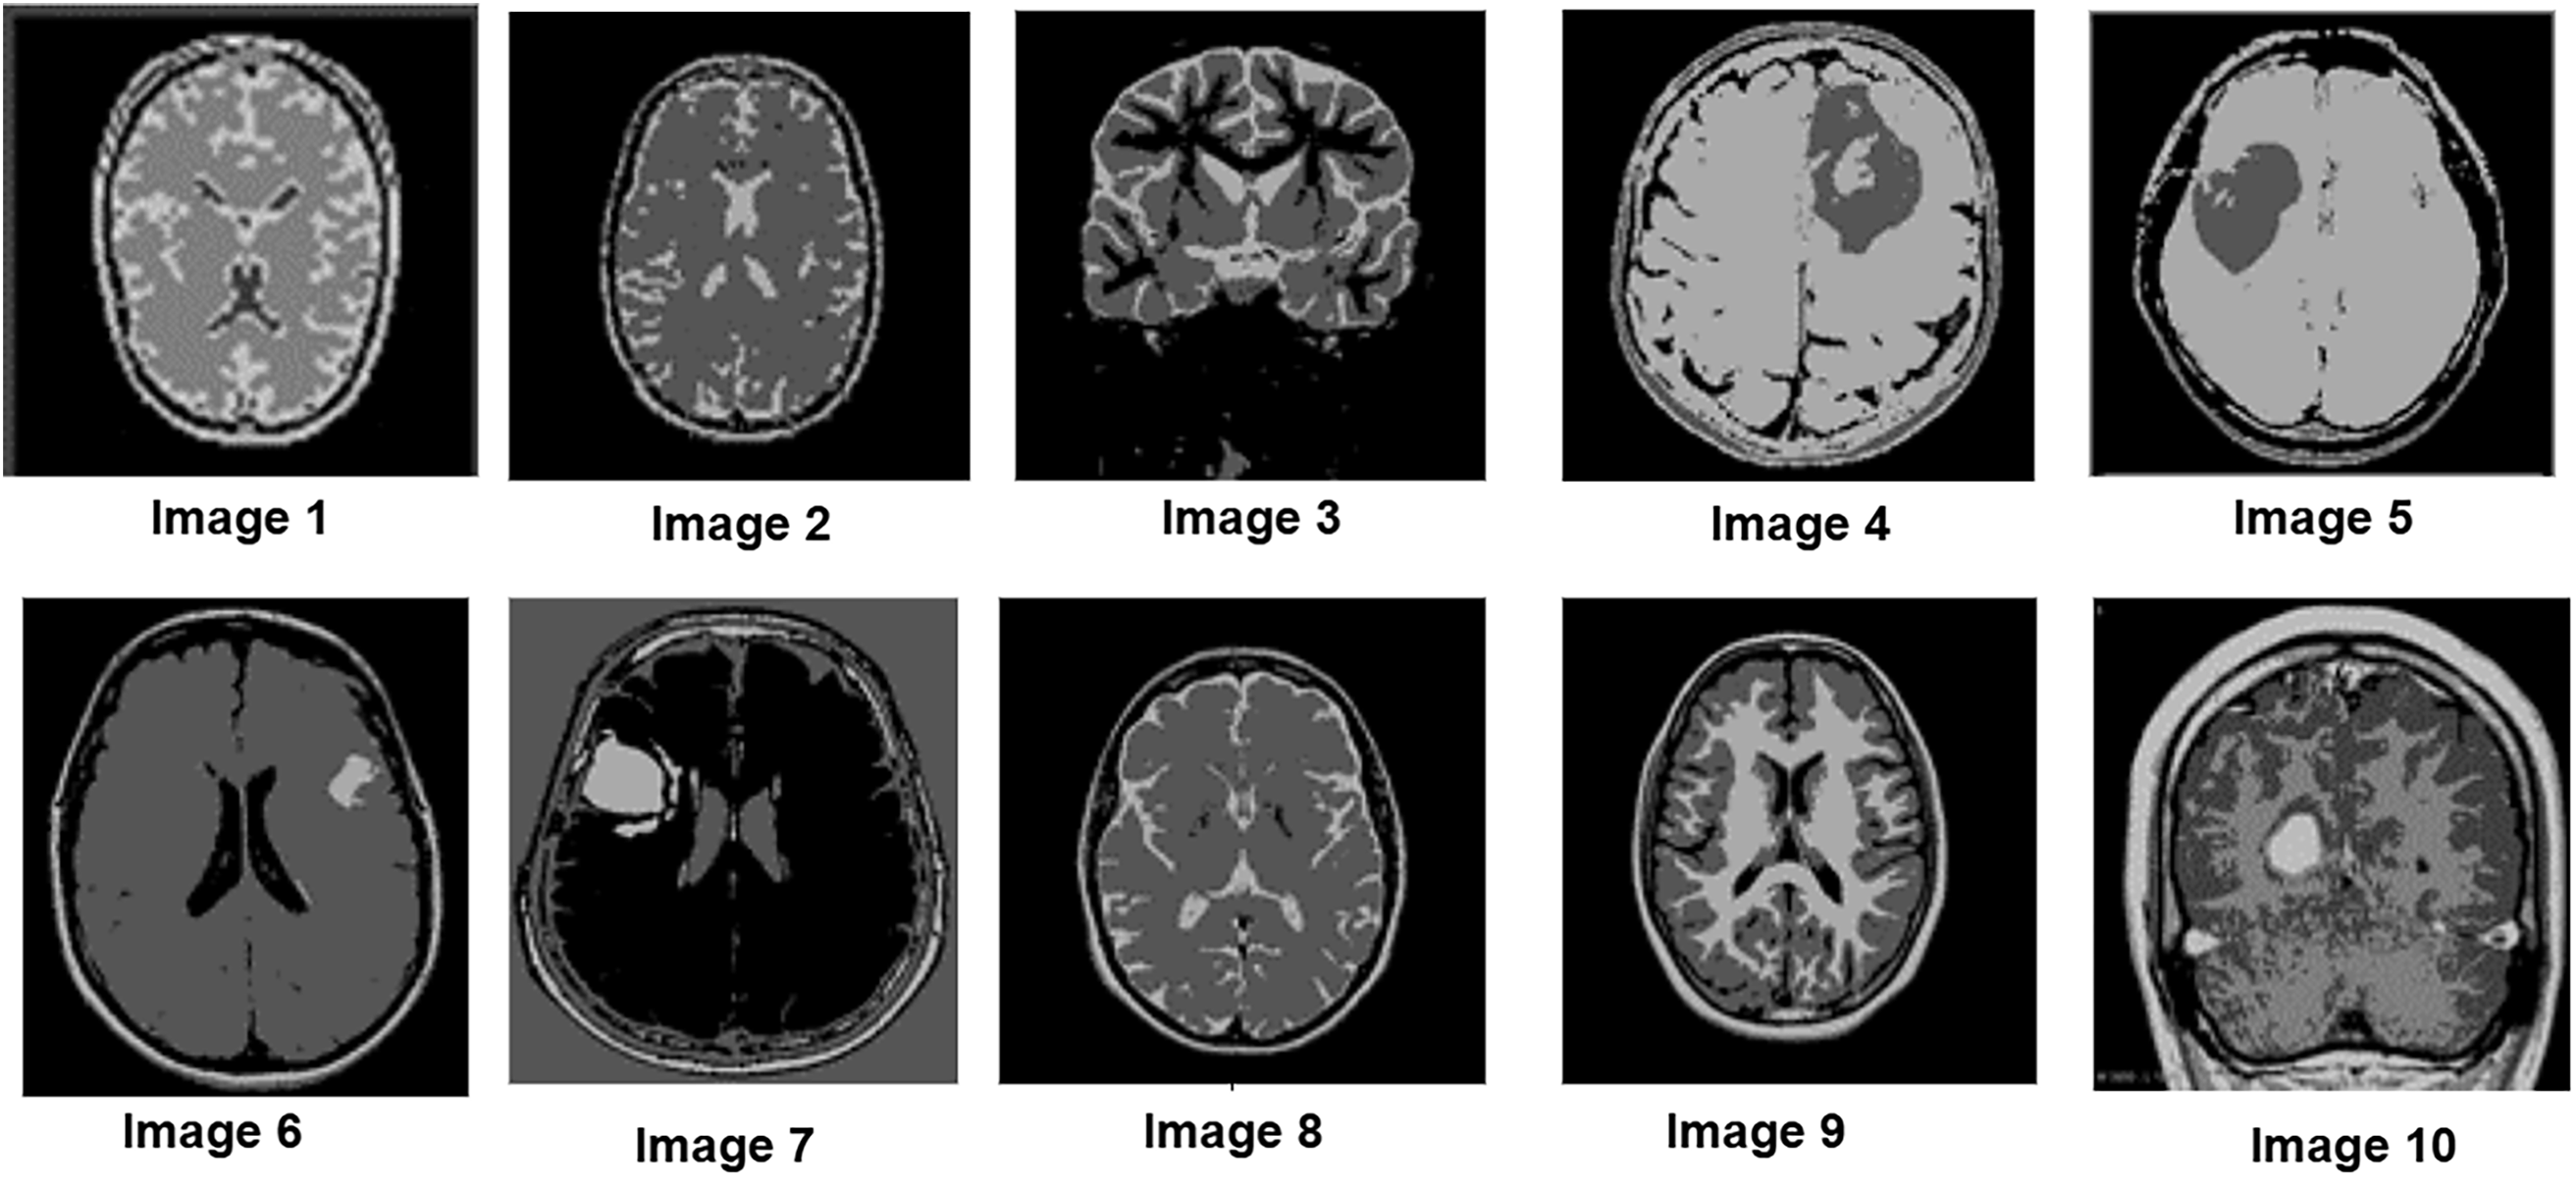

To further assess the algorithm’s performance, experiments were conducted on a clinical MRI dataset from Kaggle, which includes a variety of tumor patterns with different intensity distributions. The segmentation performance of the P-GWO-FCM method was compared to that of FCM and sequential GWO-FCM. The effectiveness of these three methods was evaluated using the DBI, PEI and PCI metrics, with the results presented in Table 4. Fig. 5 showcases a selection of MRI images from the clinical dataset used in the experiments, displaying 10 images of varying sizes to demonstrate the robustness of the proposed approach. These images were segmented using all three algorithms. Fig. 6 illustrates the segmentation results obtained for these 10 brain MRI images using the P-GWO-FCM method.

Figure 6: Segmentation results on 10 clinical MRI images from the Kaggle dataset using the proposed P-GWO-FCM. The algorithm partitions the image into C = 5 clusters (background, GM, WM, CSF, tumor)

In this context, the number of clusters was set to C = 5 to simultaneously capture background, GM, WM, CSF, and tumor. While tumor annotations are available in the dataset and used for metric evaluation, the healthy tissue clusters provide additional anatomical context around the tumor.

A visual analysis of the segmented images reveals that the P-GWO-FCM method excels in clarity, detail preservation, and precise delineation of tissue boundaries.

The results in Table 4 provide a comprehensive comparison of P-GWO-FCM, traditional FCM, and Sequential-GWO-FCM, demonstrating that P-GWO-FCM consistently outperforms the other methods across various evaluation metrics. These metrics assess clustering quality, particularly in terms of cluster compactness, separation, and the clarity and reliability of cluster assignments. Regarding the DBI, which evaluates clustering quality by measuring compactness and separation, P-GWO-FCM achieved an average DBI value of 0.30, significantly lower than those of FCM and sequential-GWO-FCM. This result indicates better cluster definition and separation, improving segmentation quality. The PEI, which quantifies uncertainty in membership assignments, further supports the robustness of our approach, as P-GWO-FCM attained an exceptionally low average PEI value of 0.25. This low PEI value reflects the minimal overlap between clusters, demonstrating the algorithm’s ability to assign data points with higher confidence and precision. Additionally, the PCI measures clustering fuzziness and further demonstrates the superiority of P-GWO-FCM. The algorithm achieved an impressive average PCI value of 0.91, indicating clearer partitioning with reduced fuzziness. This high PCI value, consistent across all test images, confirms that cluster memberships are predominantly close to 0 or 1, leading to more definitive segmentation. These quantitative results are consistent with the qualitative analysis shown in Fig. 6, where the lower DBI and PEI values obtained by P-GWO-FCM clearly correspond to more coherent and visually accurate segmentations compared to FCM and sequential GWO-FCM. It is also worth noting that the integration of Fuzzy Entropy into the fitness function enhances robustness against noise and uncertainty. Compared to the standard FCM objective, the FE-based formulation reduces DBI and PEI values, indicating more compact and reliable clusters, which further contributes to the superior performance of the proposed framework.